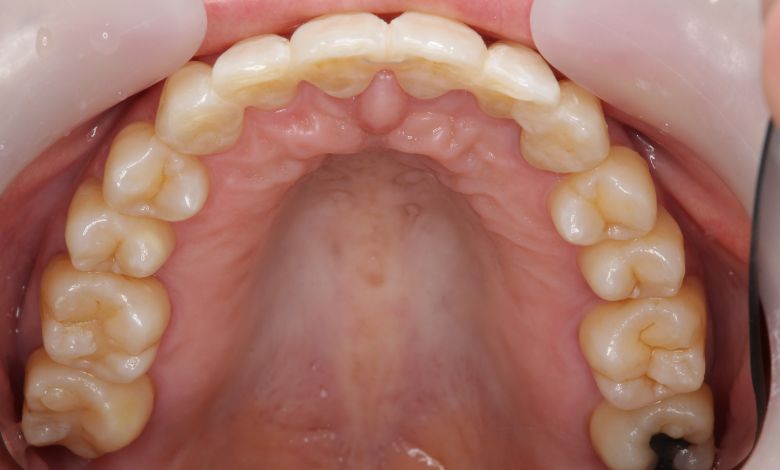

正常な咬合関係が確立され、前歯の自然なアーチと歯軸も整い、歯列全体が滑らかなカーブを描く美しい歯並びに

精密検査の結果、当院では抜歯を行わず、歯列弓の拡大によってスペースを確保し、非抜歯での矯正治療を選択しました。歯列の叢生(ガタガタ)は解消され、機能的かつ審美的に優れた咬合が得られました。

叢生が解消され、歯列全体にわたり滑らかで調和のとれた配列が得られています

歯列弓はV字型から自然でゆったりとしたU字型へと広がり、唇側に転位していた犬歯も正しい歯列内に整列されています。

歯列弓の側方拡大により適切なスペースが確保され、歯が綺麗に並んでいます